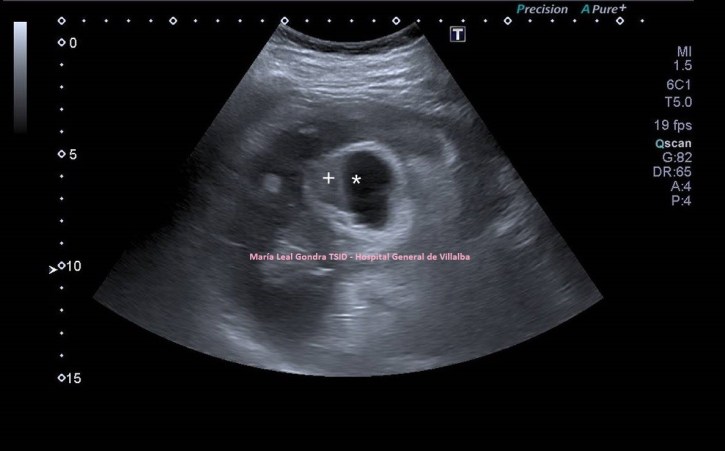

En la exploración objetivamos una glándula tiroidea aumentada de tamaño, sin imágenes nodulares, pero si heterógenea toda ella con afectación global en ambos lóbulos tiroideos. Semiológicamente se observa una y/o hiperplasia glandular y es muy significativo un abombamiento anterior de la glándula, con unas medidas elevadas discretamente respecto de sus medidas en rango de normalidad, es decir, la paciente tiene bocio no nodular y además alteración en la ecogenicidad de la glándula, pero lo más llamativo fue cuando puse el doppler para estudiar la vascularización de ambos lóbulos tiroideos. Era una vascularización elevada, mucho más que la normal vascularización de esta glándula. Es el conocido Infierno Tiroideo.

Lo primero, reconoce siempre la normalidad para poder identificar anormalidad. En la imagen 1 tienes una imagen normal de ambos lóbulos tioideos en un corte axial (nos sirve para repasar anatomía básica), en la imagen 2 un corte longitudinal de uno de los lóbulos con su vascularización típica. Bien guarda en tu cabecita estas dos imágenes y ponte en modo concentración para descubrir los cambios semiológicos en el caso de la paciente referida con anterioridad.

1

2

En la imagen 3, el corte axial de ambos lóbulos tiroideos afectados. Compara imagen 1 e imagen 3 y te vas a dar cuenta como a veces, en el primer segundo la exploración ya sabes que la glándula es patológica, como es la imagen 3.

3

Ahora, en el caso que estas viendo hoy, con la información clínica de la que disponemos y lo que nos cuenta la paciente observamos las siguientes imágenes. Sumada a la imagen 3 te enseño un corte longitudinal de uno de los lóbulos tiroideos en la imagen 4. En la imagen 4 observas un lóbulo heterogéneo (diferentes tipos de grises) cuando deberíamos ver una glándula homogénea.

4